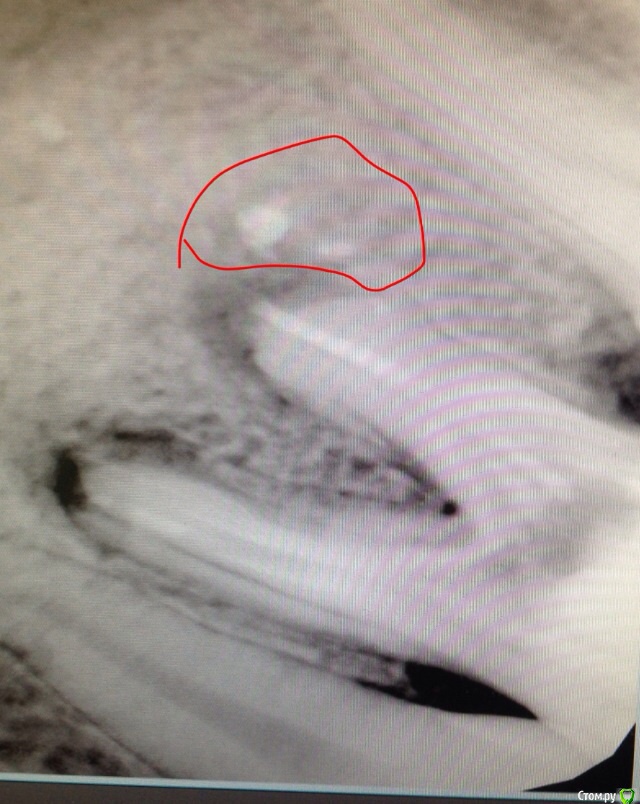

murlisa Опубликовано 3 апреля, 2017 Поделиться Опубликовано 3 апреля, 2017 может есть тут, те кто сталкивался с подобным, или даже стоматологи.Вобщем я лечу зуб, на котором стояла пломба еще давно- лет 7. Так вот после двух Гв кормлений, он начал буквально трещать по швам, весь потемнел, появились сколы, трещины. еще до второй беременности, когда я лечила все зубы, стоматолог поглядывала на него , и тогда предлагала поставить коронку, но я еле еле отошла от коронки на другой стороне нижней челюсти, и я сказала что повременим, и вот забеременела , откормила 2 года. И вот, взялась таки за него.Напримеме врач сделала снимок, (1фото)и сказала что у корня зуба, цитирую: "кальций", вскрыла, прочистила глубоко каналы, поставила пульпосептин, зуб после этого очень сильно болел и пульсировал пять дней, затем успокоился. Через две недели я пришла на повторный прием, и повторный снимок показал что ситуация ничуть не изменилась,(2 фото)и она поставила мне другое лекарство (не помню название). и вот сегодня я пришла на прием в третий раз. и опять та же картина(((( она развела руками, сказала что бессильна, отправила к другому врачу в другую клинику, дала мне их контакты. Добавила еще, что был похожий случай у одного мужчины, который после таких долгих мучений "психанул" и удалил его Ссылка на комментарий

red_butler Опубликовано 3 апреля, 2017 Поделиться Опубликовано 3 апреля, 2017 это силер, пломбировочный материал, он не рассосется. 1 Ссылка на комментарий

shishok Опубликовано 3 апреля, 2017 Поделиться Опубликовано 3 апреля, 2017 И он,как правило,никому не мешает и не влияет на прогноз лечения. 1 Ссылка на комментарий

murlisa Опубликовано 3 апреля, 2017 Автор Поделиться Опубликовано 3 апреля, 2017 И он,как правило,никому не мешает и не влияет на прогноз лечения.еще одна врач сказала что это метапикс Ссылка на комментарий

red_butler Опубликовано 3 апреля, 2017 Поделиться Опубликовано 3 апреля, 2017 а что делать?с тем что Вы называете «кальцием», ничего делать не нужно Ссылка на комментарий

murlisa Опубликовано 4 апреля, 2017 Автор Поделиться Опубликовано 4 апреля, 2017 с тем что Вы называете «кальцием», ничего делать не нужноспасибо. сегодня была на приеме, так и сказали, что это белое - ерунда, основная проблема на снимке оказалась в черном воспалении. его лечим. врач сказала что надежда спасти зуб все еще есть.... но лечение будет долгим и мучительным ....... Ссылка на комментарий